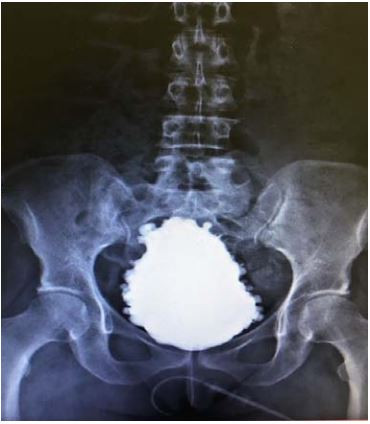

Uretrocistografia (fase miccional):